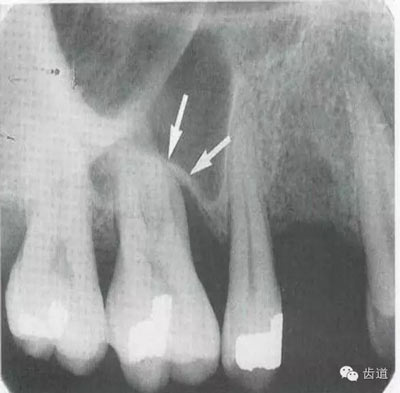

常見(jiàn)于下頜前牙區(qū),在牙根之間的牙槽骨內(nèi)并與牙長(zhǎng)軸平行的密度低的條狀影像。此為小血管進(jìn)入牙槽突的影像。